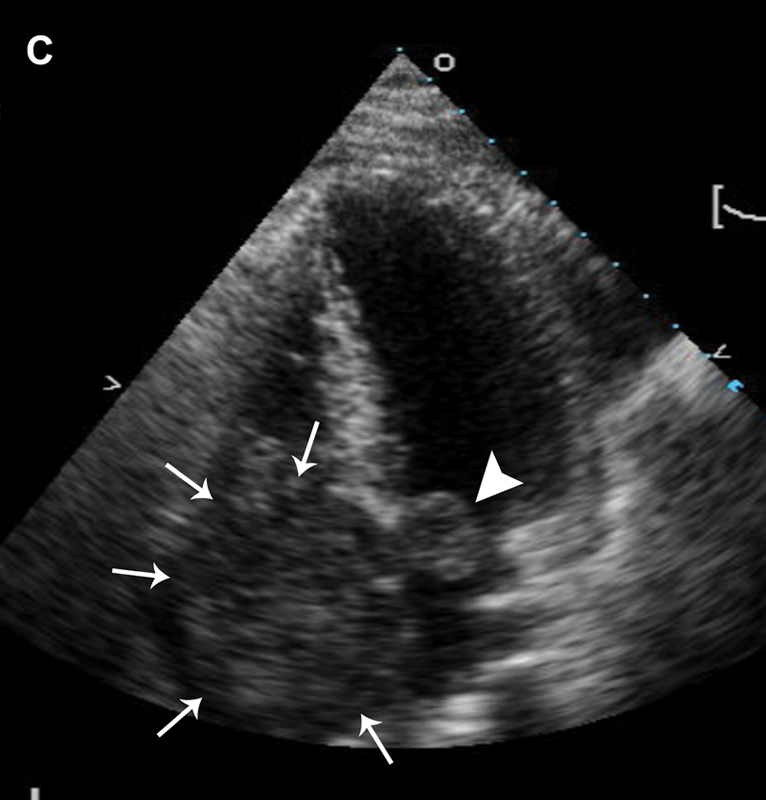

فحوصات تشخيصية لبعض امراض القلب والشرايين التاجية